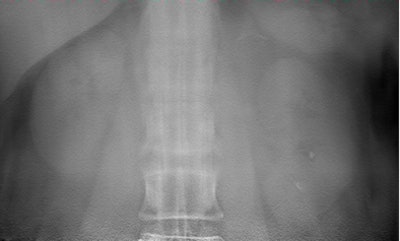

![]() |

| Two lithiasis in left kidney, seen on both techniques but much clearer on the tomosynthesis image (above), as well as nice visualization of the contour of the kidney. Images courtesy of Dr. Koen Mermuys. |